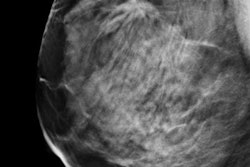

A team led by Dr. Karsten Juhl Jørgensen wanted to determine the extent to which mammography resulted in overdiagnosis, or the detection of cancers that would never pose a threat to the health of women being screened (Ann Int Med, January 10, 2017). Cochrane researchers for decades have been harsh critics of breast screening, which they believe mostly detects indolent cancers and ductal carcinoma in situ (DCIS). This week's study is no exception.

Effective breast cancer screening should detect early-stage cancer and prevent advanced disease. However, overdiagnosis occurs when mammography detects small tumors that may never affect the patient's health during a lifetime, Jørgensen and colleagues wrote. The researchers emphasized that "the problem with overdiagnosis is that it exposes patients to the potential harms of treatment, such as surgery, chemotherapy, and radiation, without a clinical benefit."